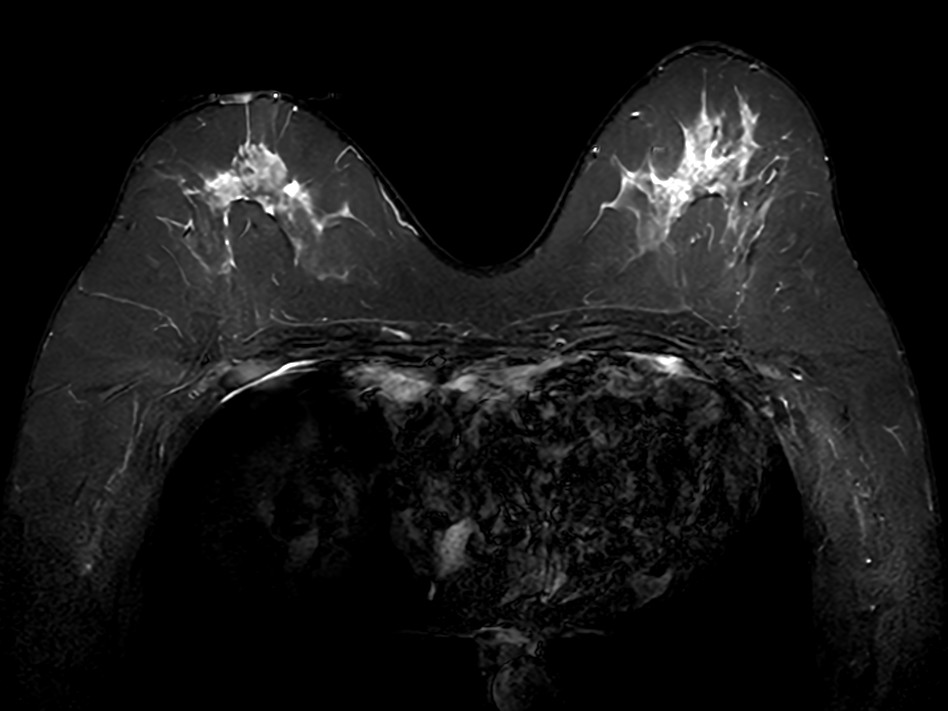

Axial 3D mDIXON gado (MPR)